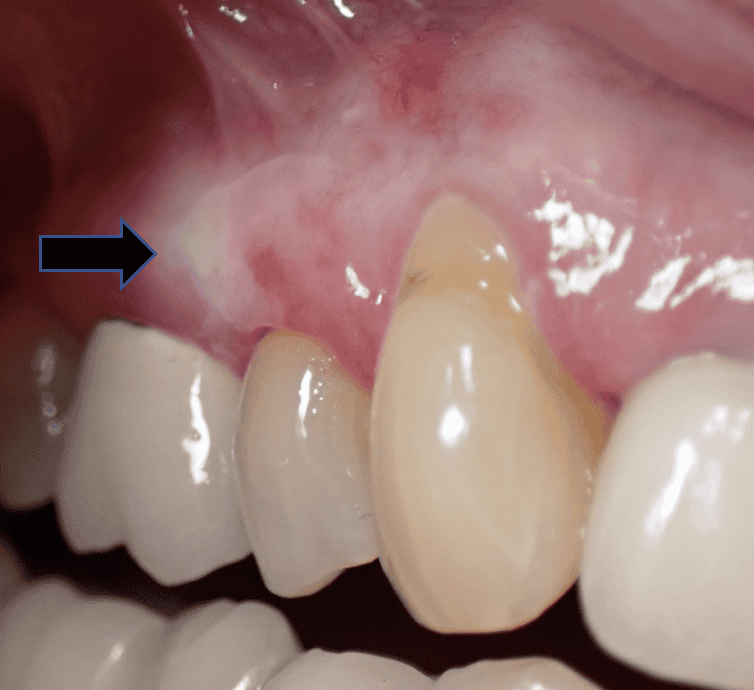

لکوپلاکیا لثه (Leukoplakia)

–ظاهر: یک لکه یا پلاک سفید ضخیم روی لثه، زبان یا داخل گونه. برخلاف برفک، این لکه به هیچ وجه با خراشیدن پاک نمیشود. سطح آن ممکن است صاف یا زبر و «چرمی» شکل باشد.

-علت چیست؟ علت دقیق همیشه مشخص نیست، اما به شدت با مصرف تنباکو (سیگار، قلیان، جویدن تنباکو) و مصرف زیاد الکل مرتبط است. این یک واکنش بدن به تحریک مزمن است.